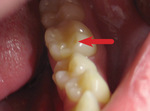

Powstanie klinicznie widzialnej zmiany wymaga częstego i długotrwałego kontaktu czynnika sprawczego z tkankami zęba.[3] Na początku rozwoju choroby pacjent nie odczuwa żadnych dolegliwości bólowych i na ogół nie dostrzega zmian. Z czasem jednak nieleczona zmiana ulega progresji, odsłaniają się kanaliki zębinowe i pojawia się wzmożona wrażliwość na bodźce termiczne, mechaniczne oraz chemiczne. Typowy obraz zmiany erozyjnej to płytkie i szerokie zagłębienia o gładkiej, twardej, błyszczącej powierzchni (ryc. 1).